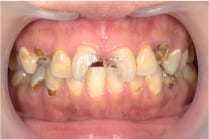

この写真の様に黒くなって穴が開き、さらにどんどん歯が崩壊し、この様な状態になってしまいます。

【27歳女性の症例】

「虫歯が気になっていたけど、忙しくてなかなか治療に行けなかった…」

そんな不安を抱えてご来院された27歳の女性。

上下合わせて16本の虫歯治療を行いました。

黒ずんでいる部分は菌が大量に増殖して歯を溶かしています。菌が出す毒素がたくさんあるという事ですから当然悪臭がします。

この様な歯があれば当然口臭がしてきます。口臭はご自身では気づきにくいので自覚がない方がほとんどですが、穴が開いている様な虫歯があれば程度の差はあれど口臭の原因になっている事は間違いありません。